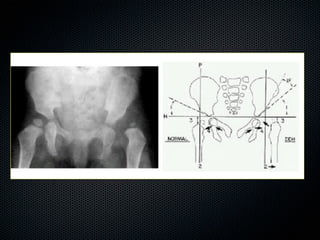

Evaluación Radiográfica

• Línea de Hilgenreiner

• Línea de Perkin

• Curva de Shenton

• Índice Acetabular 25-30º

• Cobertura Acetabular 20º

Evaluación Radiográfica • Líneade Hilgenreiner • Línea de Perkin • Curva de Shenton • Índice Acetabular 25-30º • Cobertura Acetabular 20º